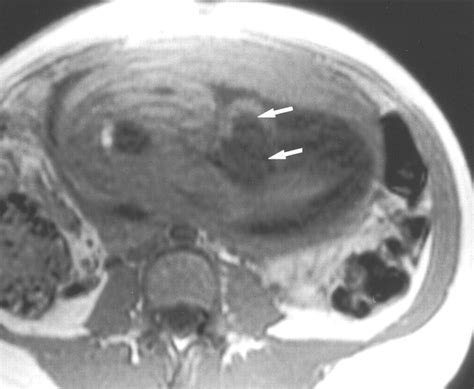

Diagnosis of an umbilical cord cyst is usually made through ultrasound imaging. During an ultrasound, the healthcare provider can visualize the cyst and assess its size, location, and any potential impact on the baby's health. In some cases, additional diagnostic tests, such as amniocentesis or fetal echocardiography, may be recommended to rule out other potential complications.